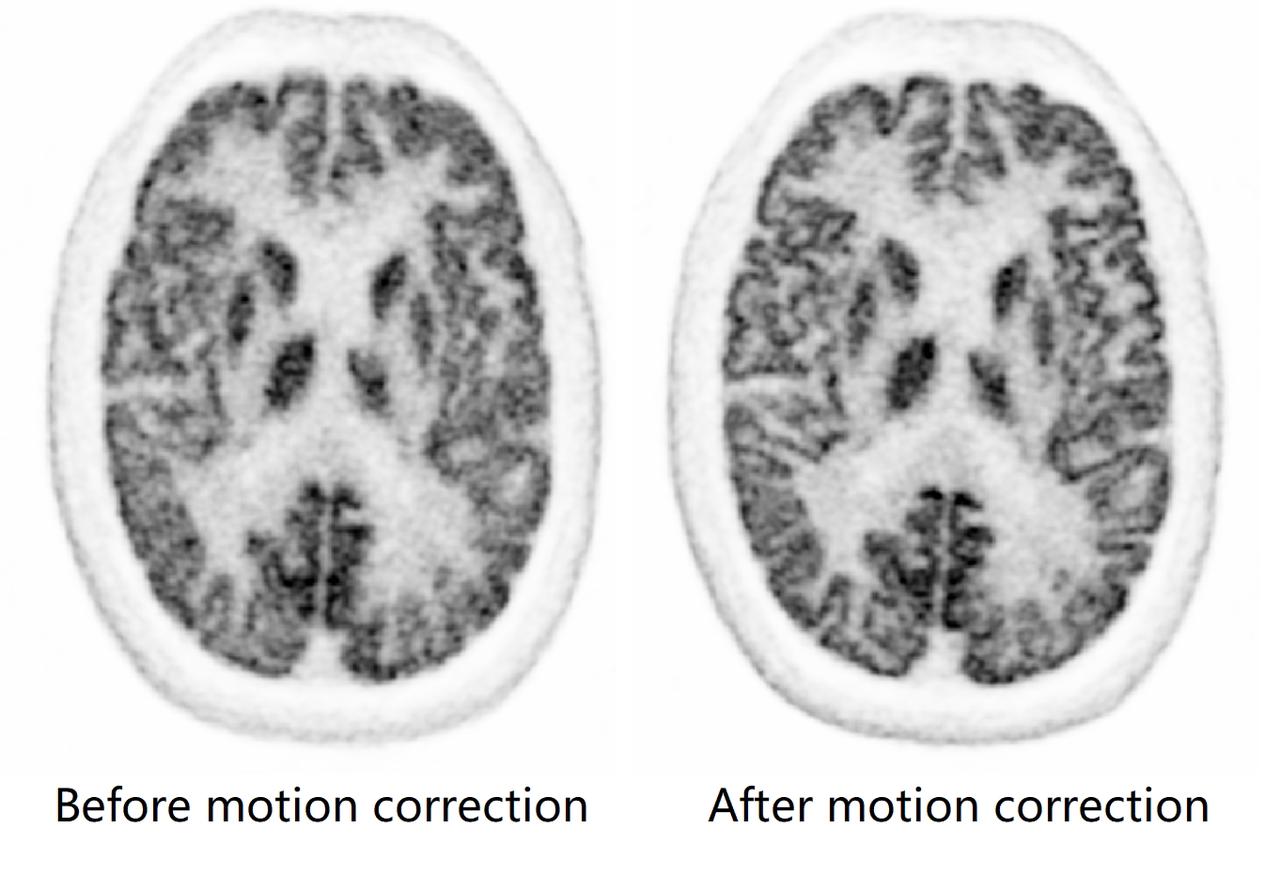

一直以来,运动伪影困扰着核医学界,扫描过程中患者任何轻微移动都会对最终的图像清晰度产生影响。NX革命性地开发实时无标注头部运动追踪,解决了头部运动造成的成像伪影问题,确保成像卓越精度。

运动伪影校正前后影像对比